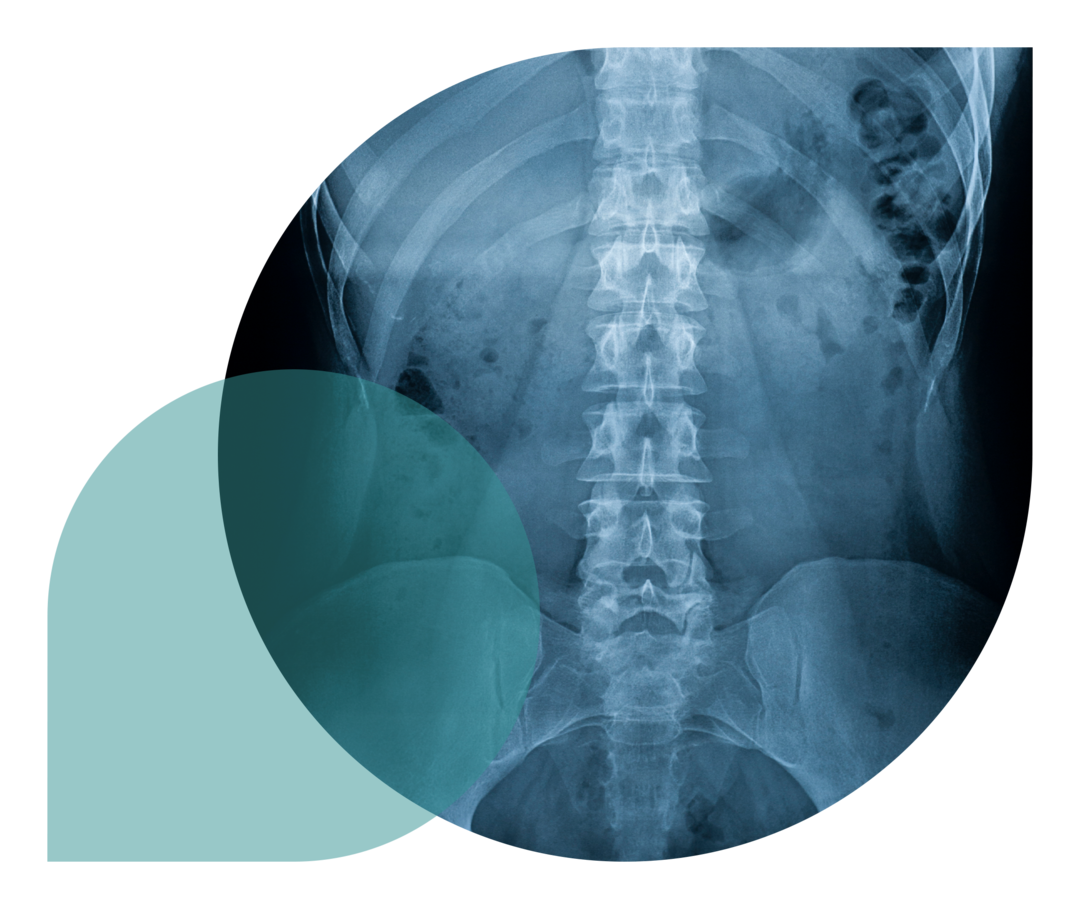

Eine wichtige Rolle bei der Diagnose von Morbus Bechterew spielen bildgebende Verfahren: Untersuchungen mittels Röntgen, Computertomografie (CT), Magnetresonanztomografie (MRT) und Ultraschall können Gelenkentzündungen, aber auch Verknöcherungen zeigen, die auf Morbus Bechterew hinweisen. Da die Frühform von Morbus Bechterew, die nicht-röntgenologische axiale Spondyloarthritis (nr-axSpA) nicht auf einem Röntgenbild erkannt werden kann, sind MRT-Bilder für eine frühe Diagnose entzündlicher Veränderungen der Kreuzdarmbeingelenke, der Wirbelsäule und der Hüftgelenke unverzichtbar. 1,2